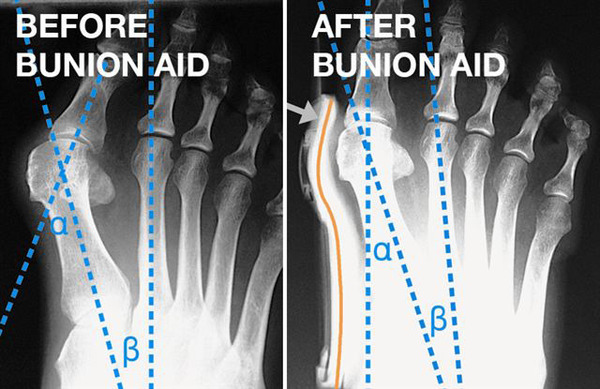

Vbočený palec nohy neboli Hallux valgus, je následný jev příčně ploché nohy. Problémy nastávají při přetížení způsobeném vysokými podpatky nebo nedostatkem místa pro prsty nohou. Bolestivé záněty vbočeného palce a pod ním se nacházejícího tíhového váčku mohou být toho důsledkem. Hallufix zmírňuje bolest, je oporou nohy při našlapování a chůzi, koriguje nesprávné postavení prstů, uvolňuje celou dolní končetinu, snižuje riziko rozvoje artrózy, je možno ji nosit v pohodlné obuvi, zlepšuje první fázi pohybu nohy, správně přiléhá k noze díky elastickému polštářku. Lze nosit před a po operačních výkonech.

1 - Objímka palce - bezbolestně koriguje polohu palce, jemně tlačí do správné polohy.

2 - Kloub - konstrukce ortézy vnucuje správný pohyb v kloubu a umožňuje aktivní korekci valgozity.

3 - Měkká stélka - ulevuje od bolesti vyplývající z tlaku nohy v botách.

4 - Metatarzální objímka - umístění v blízkosti prvního metatarzu způsobuje správné postavení nohy, čímž se noha stává štíhlejší a snadněji se nosí v obuvi.

5 - Metatarzální pelota - napomáhá klenbě přednoží a zabraňuje příčnému plochonoží